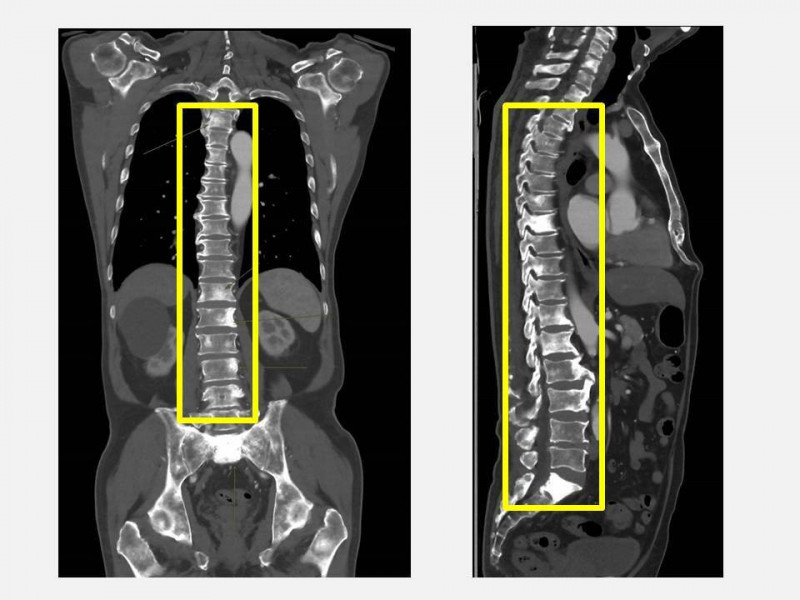

〔記者陳建志/台中報導〕70歲的余先生近來頻繁背痛,原以為只是年紀大出現的脊椎退化,只吃止痛藥加上熱敷希望能緩解,沒有積極就醫,直到子女安排接受健康檢查,意外發現攝護腺特異抗原(PSA)與鹼性磷酸酶(ALK-P)指數明顯異常,察覺可能罹患攝護腺癌且轉移,立即安排影像學檢查並轉介至泌尿科,檢查後確診為攝護腺癌合併瀰漫性骨轉移,及時治療後讓病情獲得控制。

仁愛長庚合作聯盟醫院泌尿科主任劉緯陽表示,攝護腺癌是台灣男性常見癌症,早期並無明顯症狀,患者常因為排尿困難、夜尿頻繁、血尿,或者像患者一樣出現骨痛才就醫,往往病情已屬晚期。余男因背痛接受健檢而發現異常,算是「因禍得福」,否則若再拖延,可能導致骨折、神經壓迫等嚴重併發症。